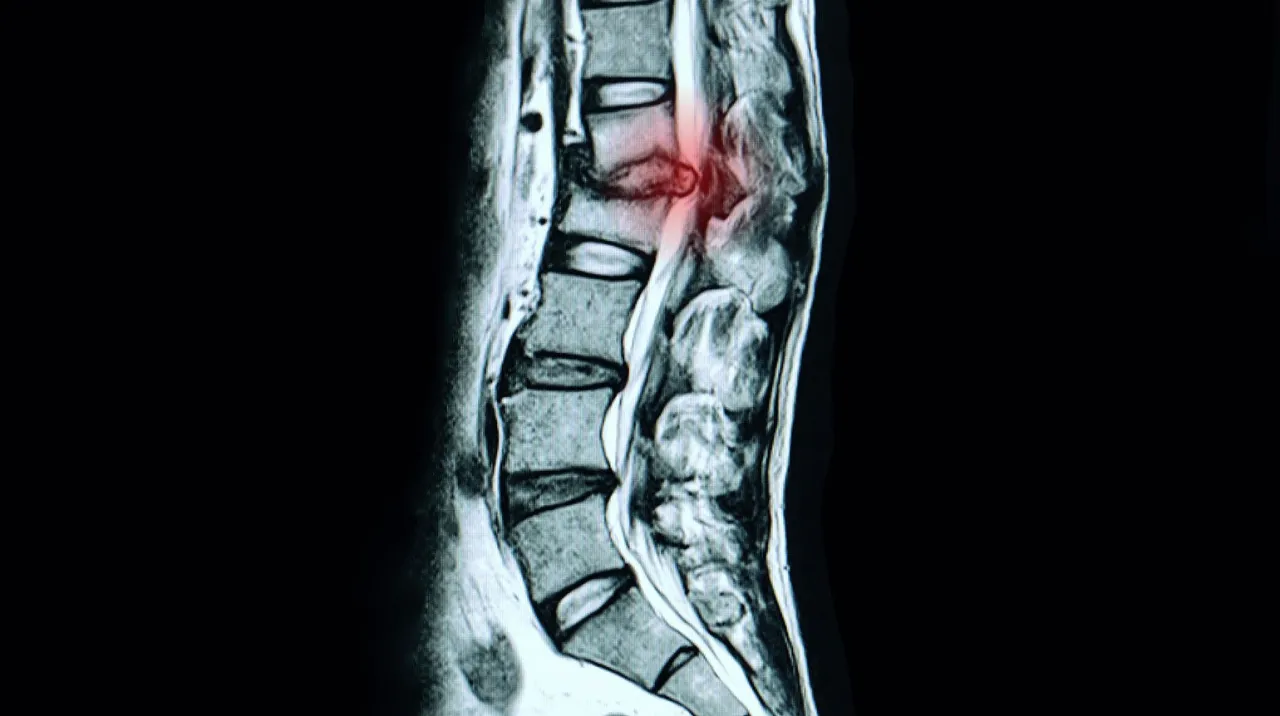

Was genau passiert bei einem Bandscheibenvorfall in der Lendenwirbelsäule?

Um die Bedeutung der Übungen zu verstehen, ist es hilfreich, kurz zu rekapitulieren, was bei einem Bandscheibenvorfall in der LWS eigentlich geschieht. Unsere Bandscheiben fungieren als Stoßdämpfer zwischen den Wirbelkörpern. Sie bestehen aus einem äußeren Faserring und einem gelartigen Kern. Bei einem Bandscheibenvorfall, medizinisch als Diskusprolaps bezeichnet, wölbt sich dieser Kern nach außen vor oder tritt sogar aus dem Faserring aus. Im Bereich der Lendenwirbelsäule ist dies besonders häufig, da hier die größten Belastungen auftreten. Wenn das ausgetretene Bandscheibengewebe auf eine der empfindlichen Nervenwurzeln drückt, die aus dem Rückenmark austreten, verursacht dies die typischen, oft starken Schmerzen, die bis ins Bein ausstrahlen können. Ziel unserer Übungen ist es, diesen Druck zu reduzieren und die natürliche Funktion der Wirbelsäule wiederherzustellen.